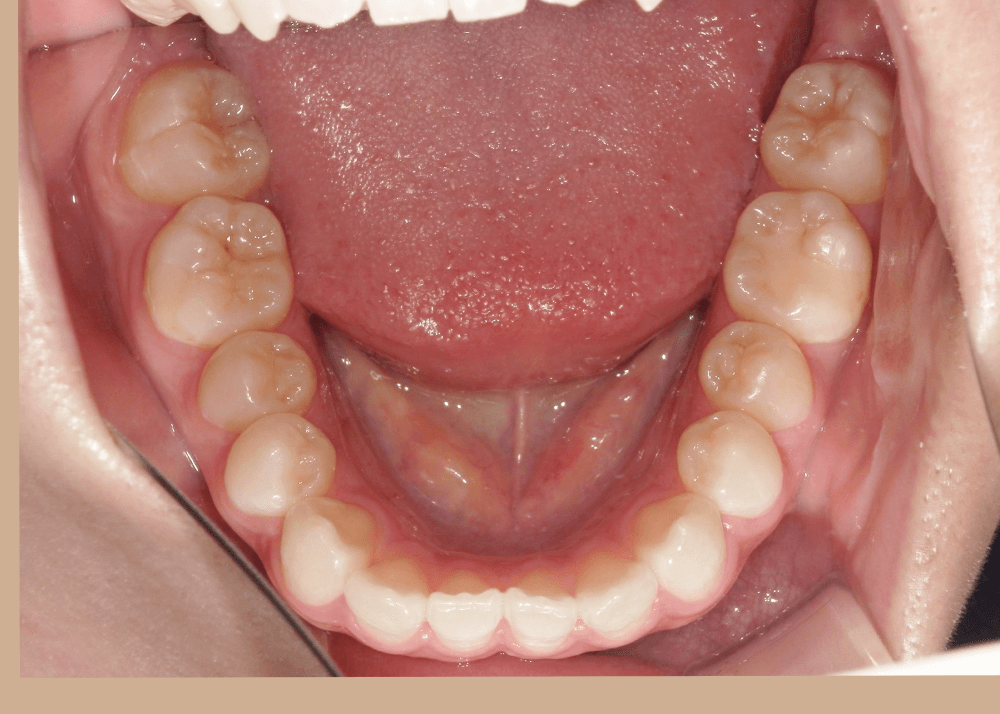

一見すると大きなガタガタはなく、歯並び自体は比較的きれいに整っているように見えます。

角度を変えて確認すると、上の前歯が前方に突出しており、上下の前歯がしっかり噛み合っていない状態(前歯部に隙間)が認められました。

このように、歯列の乱れは軽度である一方、前歯の前突および口元の突出感が認められました。

治療後は、気にされていた「口ゴボ(口元の突出感)」が改善され、自然でバランスの良い口元になりました。

隙間のあった前歯も、しっかり噛み合うようになっています。